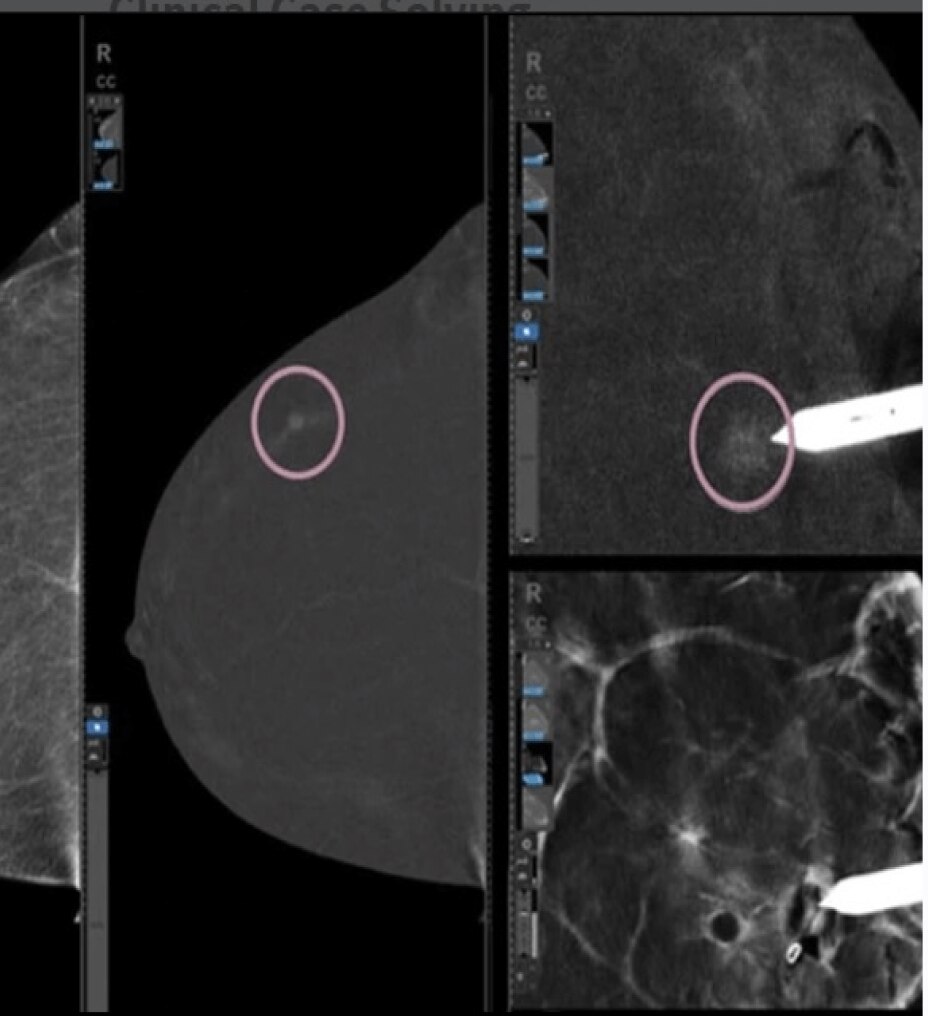

ViewPoint 6 is configurable. You can adapt its easy-to-use exam documentation screen exactly to your needs. With Quick Reports you can define templates for common findings to speed up routine work. Standard sonographer worksheets also support ACR TI-RADS™ and BI-RADS®, and are adaptable to your specific protocols.